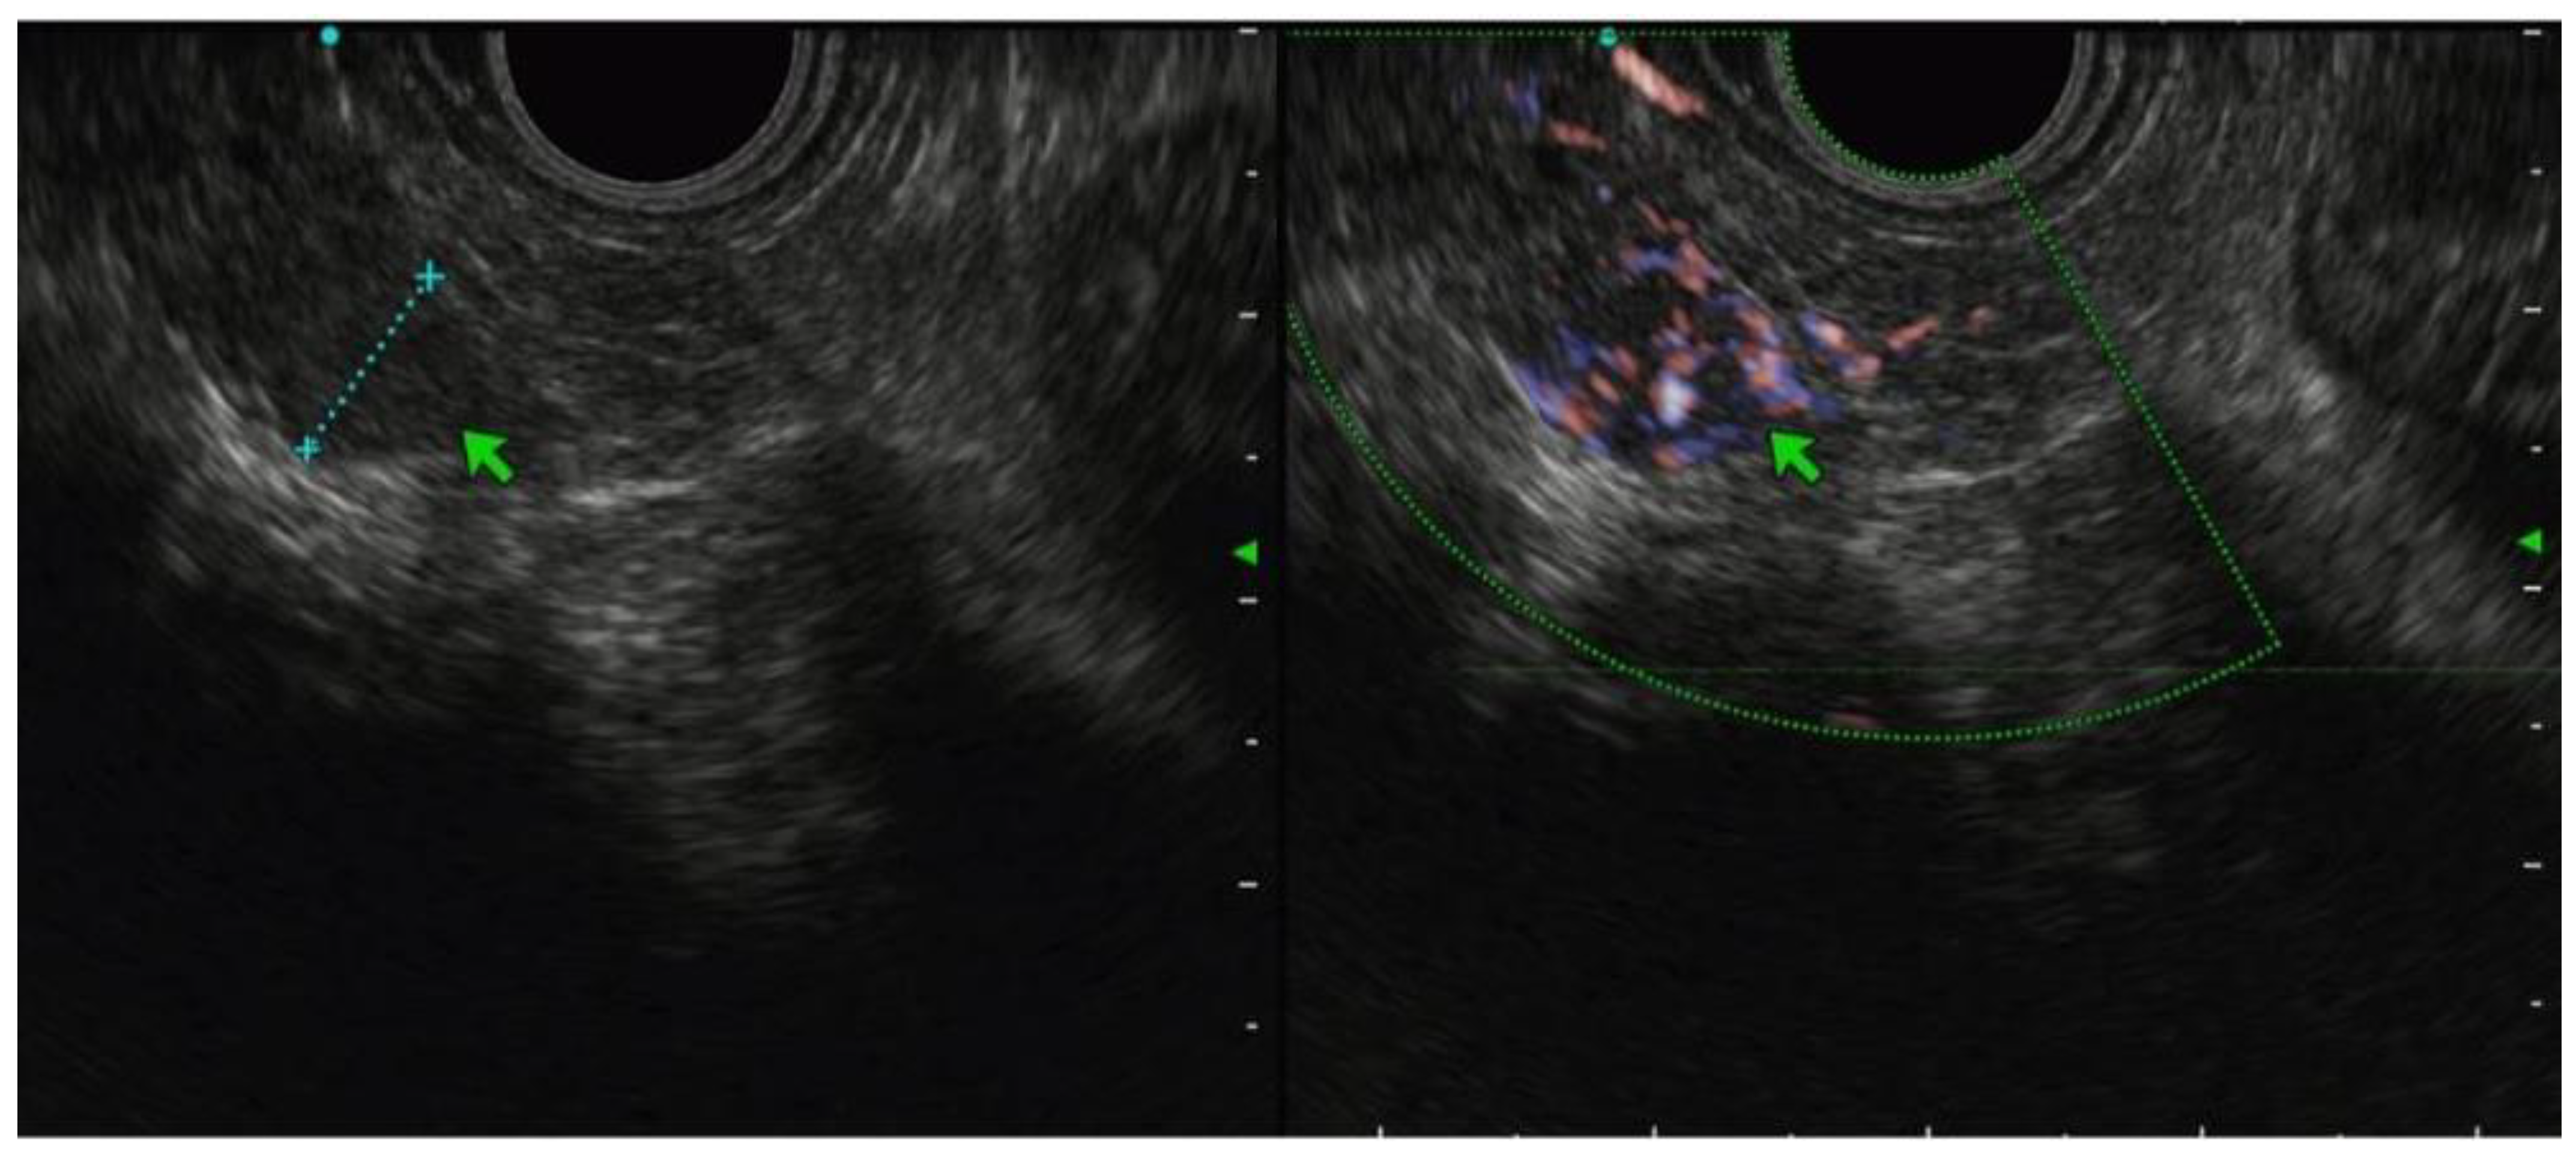

3.2. EUS Characteristics